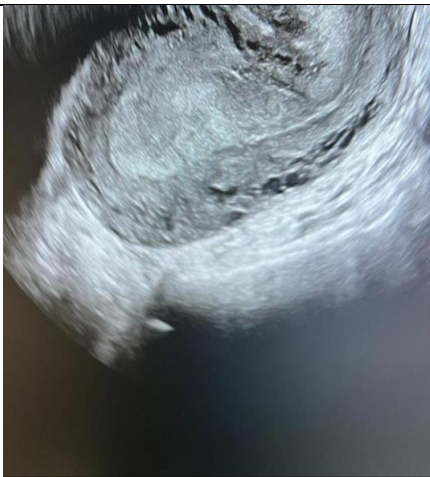

A 16-year-old lady, para 0+2 presented to the emergency department complaining of active vaginal bleeding after medical treatment of missed miscarriage. She had history of two recurrent miscarriages treated by surgical evacuation. Her pregnancy was spontaneous. Her medical history was unremarkable. Clinically she was vitally stable, soft abdomen, no tenderness no palpable masses. Speculum examination was suggestive of normal-looking cervix with bleeding from the os, uniformly enlarged 8 weeks size uterus freely mobile, no cervical movement tenderness, and no adnexal masses. An ultrasound demonstrated a gestational sac about 2.2 cm in diameter. It showed also a yolk sac and a fetal pole of 8 mm without cardiac cavity. Surgical suction and evacuation was performed under ultrasound guidance.  During the evacuation, the gestational sac was noted to be below the suction tube, the procedure was aborted. The intrauterine products were sent for histology which showed fragments of endometrium, blood clots and fibrosed chorionic villi, no evidence of malignancy. Upon reassessment, she was still complaining of the vaginal bleeding. Beta human chorionic gonadotropin was 1450. A Trans abdominal & trans vaginal ultrasound scan showed empty cavity with thick endometrium, a gestational sac below the line of endometrium with a yolk sac and fetal pole without cardiac activity, embedded in the myometrium (Fig.1&2&3&4) .The use of 3-D ultrasound helped in confirming the diagnosis of intramyometrial pregnancy, providing highly informative and detailed imaging to support accurate clinical assessment (Fig.5&6). In view of her parity and future fertility medical treatment was discussed with and accepted by the patient. Methotrexate was administered with a single dose of 50mg given intramuscularly on day 7, the drop was less than 15%. The patient received a second dose of methotrexate .The patient was displaced due to war circumstances. She then continued to have serial pregnancy tests, not able to have quantitative B-HCG test. Her pregnancy test became negative eventually then her menstrual cycle resumed back with regular intervals.

FIG.3

FIG.4

Figure 3

Figure 4